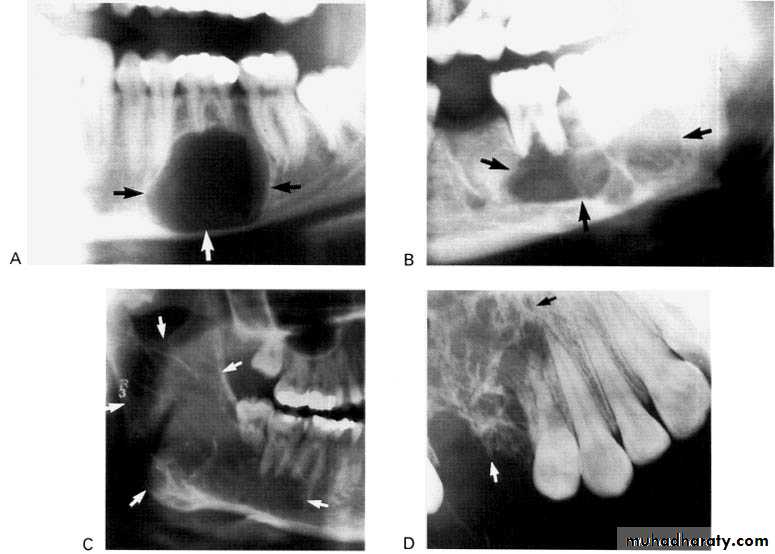

5-year-old boy showing the typical bilateral multilocular lesions of

cherubism affecting the mandible (arrowed).Multiple but separate radiolucent lesions

Radiographically :

• Multiple radiolucent areas in the interdental & interradicular bone.

• teeth seem to hang in air. Exfoliation of teeth & teeth germ are common, ulceration of overlaying mucosa.

• Multiple radiolucent foci seen in the skull & long bone of the skeleton, lesion in the skull give appearance of geographic map , with skull enlargement .

Increased secretion of parathormone, causes generalized skeletal bone resorption leading to osteopenia (generalized decrease in bone density).Single or multiple radiolucency in the maxilla & mandible.

• Loss of normal bone trabeculation & replaced by fine poorly calcified bone spicules that give ground glass appearance.

• Missing of lamina dura.

Loss of the lamina dura and the granular texture of the bone pattern.

Radiographically; multiple punched-out in the jaw & skull, the peripheral border is smooth & irregular in comparison with the Histiocytosis-x.